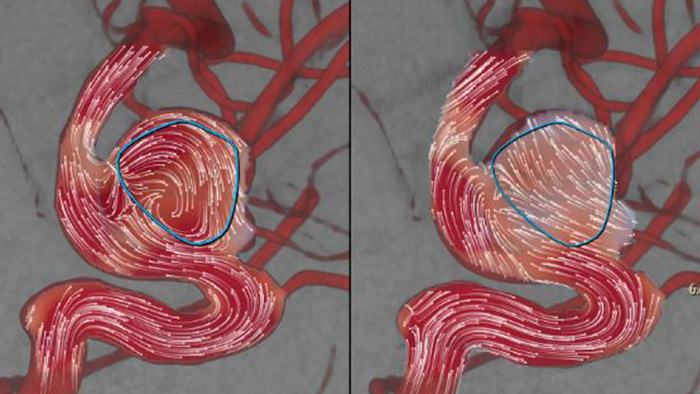

AneurysmFlow est conçu pour fournir des informations pertinentes avant et après le déploiement du déviateur de flux. Il visualise et quantifie les changements de flux pour une plus grande confiance dans l’efficacité de la procédure.